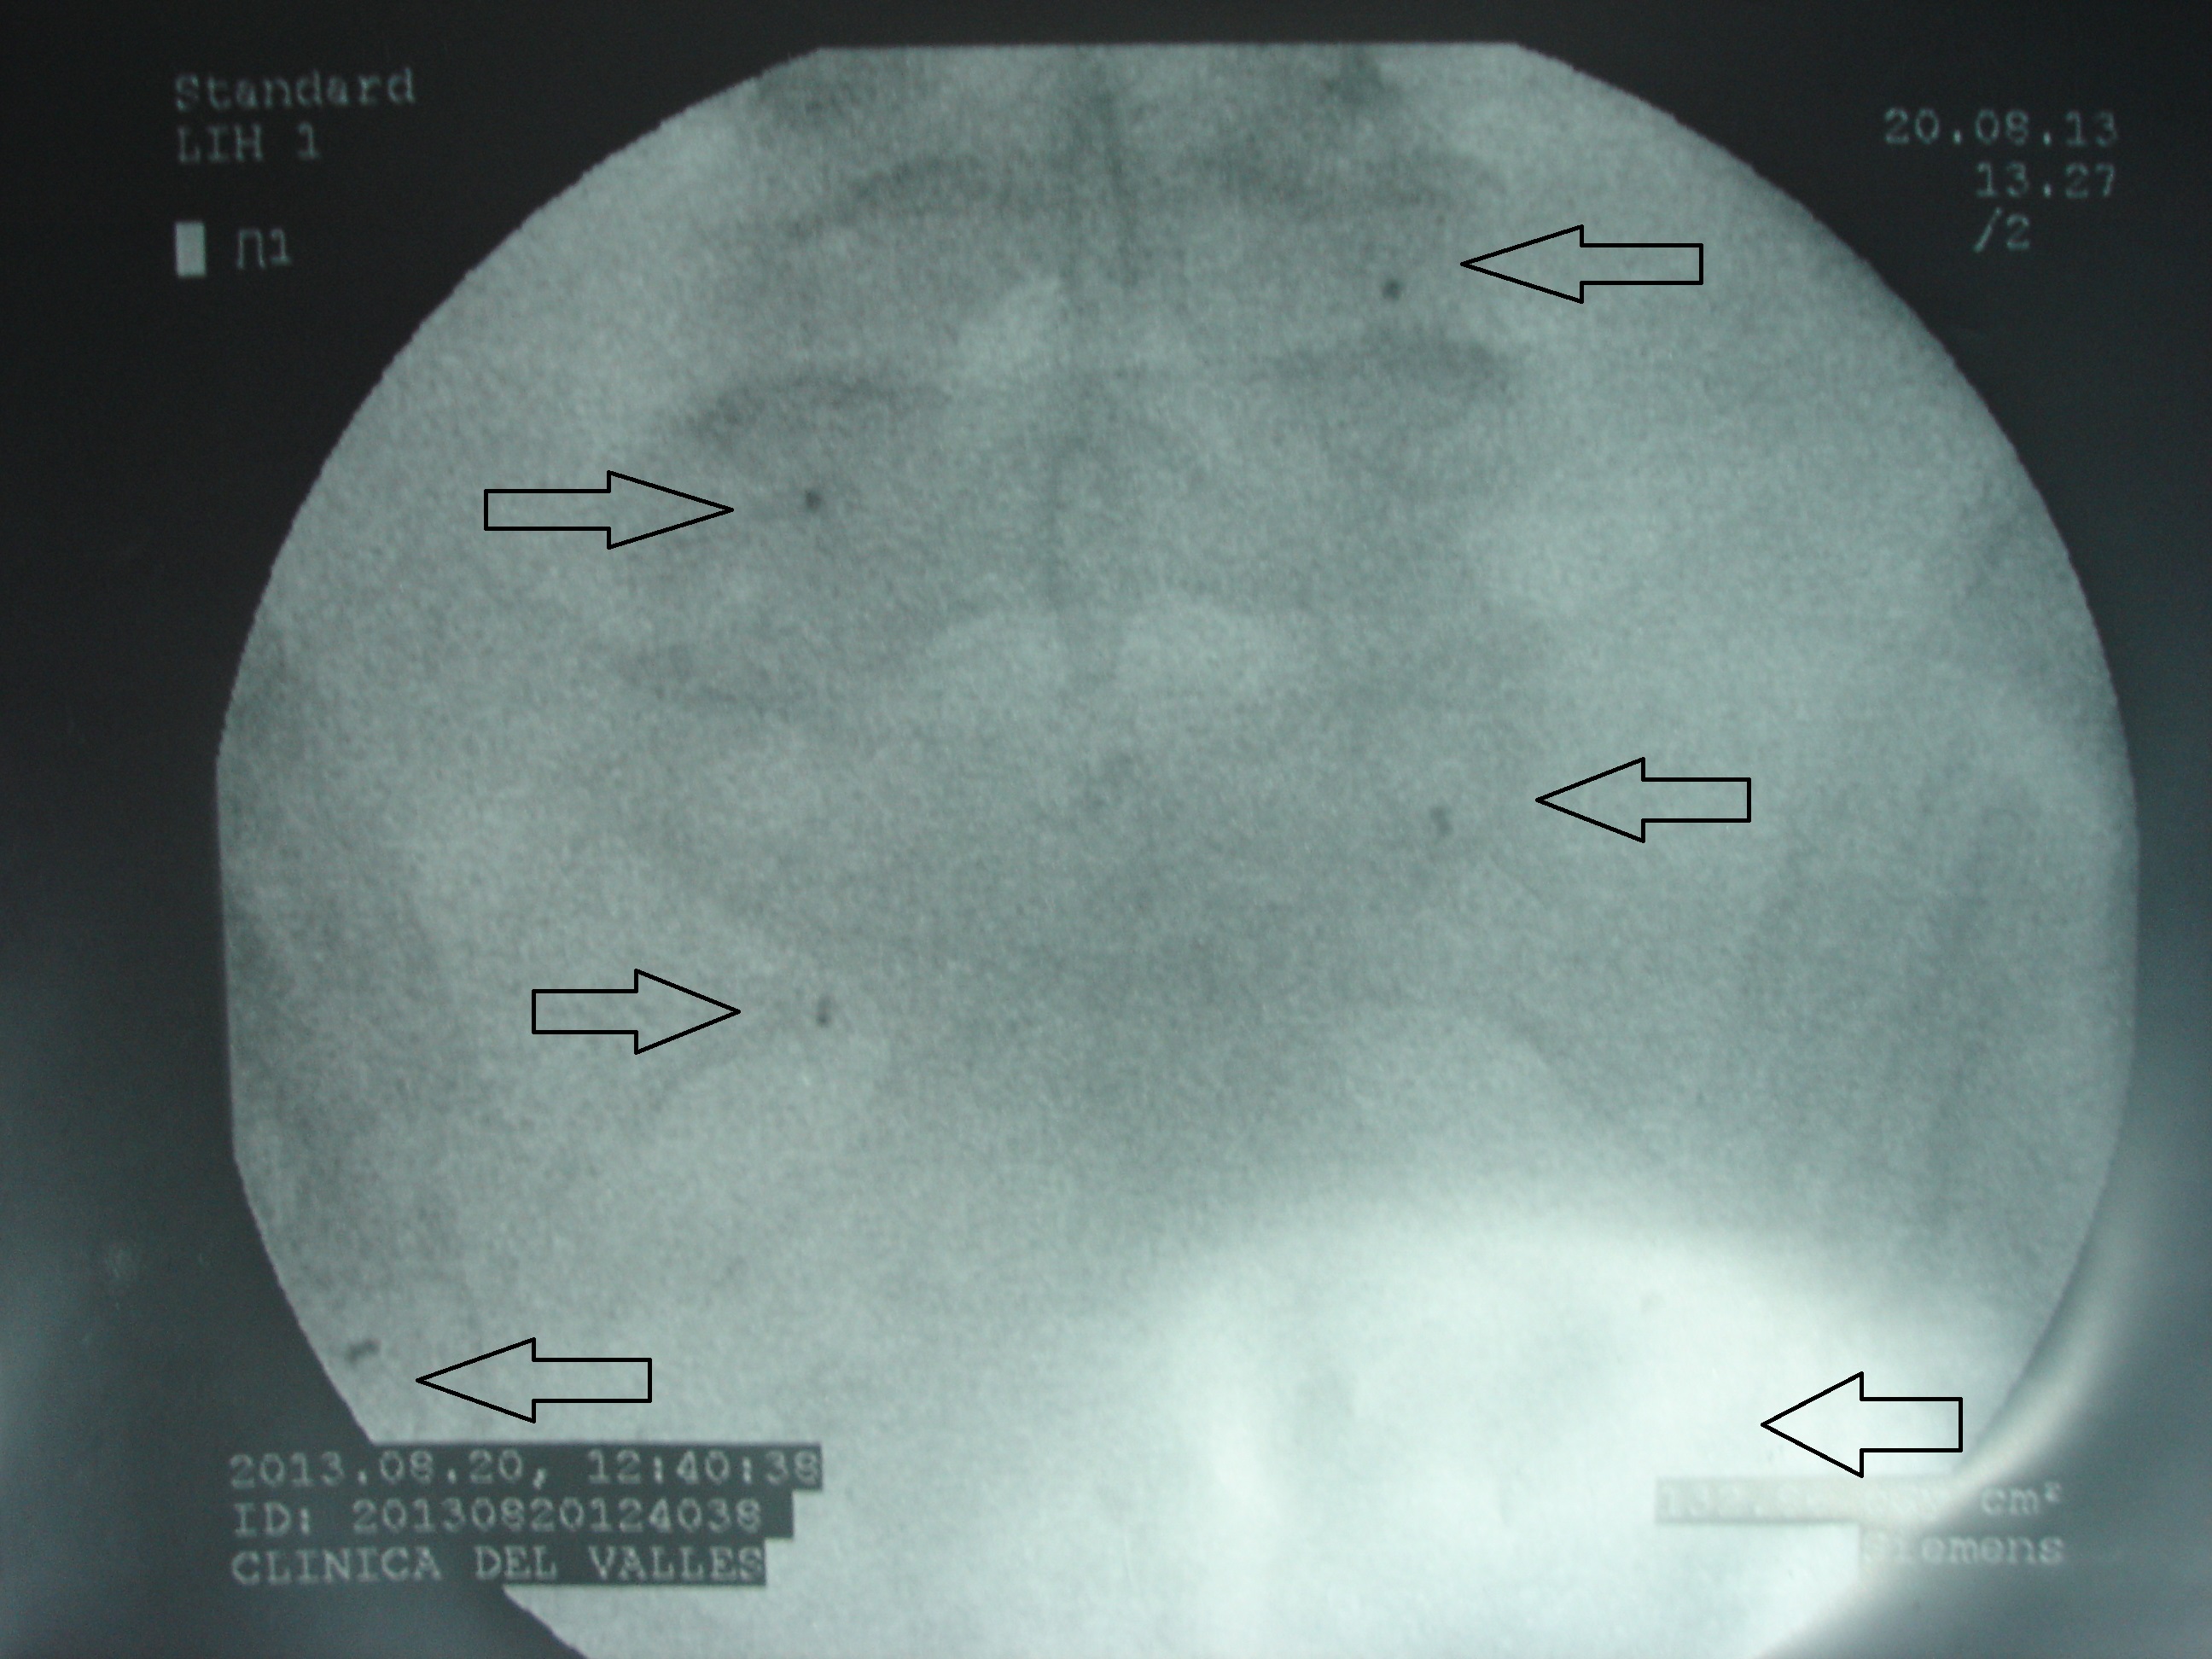

Las imágenes a continuación pertenecen a un caso con una remisión sintomática casi completa y un grado muy alto de satisfacción de la paciente tratada.

En las imágenes de RX y RMN se observan los cambios degenerativos (señalados en rojo las articulaciones interapofisarias artrósicas), también la presencia de múltiples hemangiomas, y las imágenes intraoperatorias de control de los implantes de oro (con flechas).